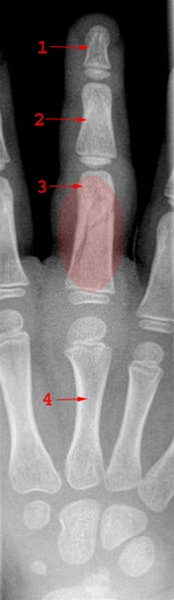

Skråfraktur uden fejlstilling gennem tredje fingers proksimale falanx. Bemærk at der er tale om en barneknogle med åbne epifyselinjer.

1. Distale phalanx

2. Midterste phalanx

3. Proximale phalanx

4. Metakarp